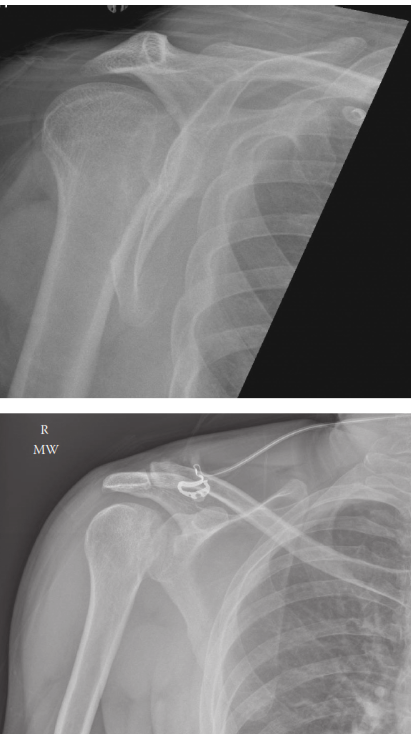

A 35-year-old woman fell from a ladder, injuring her right shoulder. These are her radiographs. 1. What do th…

Management of Proximal Humerus Fracture 1. Describe these radiographs. Show Answer Show Explanation 2. How wo…